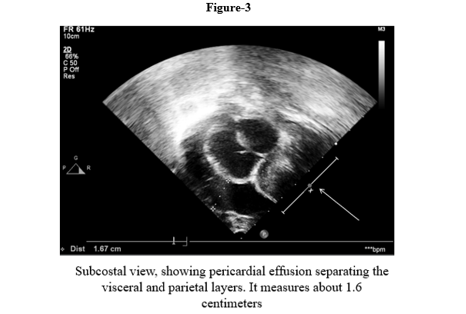

We report a four-month-old girl who presented in sudden cardiorespiratory collapse to illustrate an uncommon cardiac first sign of MTO1-related disease. The infant arrived hypotensive and obtunded with severe metabolic acidosis (pH 6.59; lactate 29 mmol/L). Chest radiograph showed cardiomegaly and bedside echocardiography revealed a large circumferential pericardial effusion producing compression of the right heart together with concentric left-ventricular hypertrophy. Emergency pericardiocentesis drained 120 mL of serous fluid and produced only transient improvement; over a prolonged PICU stay she had recurrent sterile effusions, four failed extubation attempts, refractory lactic acidosis, renal dysfunction and progressive bradycardia. Whole-exome sequencing identified a homozygous pathogenic MTO1 variant (NM_012123.4:c.1232C>T; p. Thr411Ile); both parents were heterozygous carriers. The family history included consanguinity and a sibling who died in early infancy after a similar illness. Despite maximal supportive care, she died on day 40 from cardiogenic shock and multiorgan failure. The case highlights that recurrent sterile pericardial effusion in an infant with hypertrophy and marked hyperlactatemia should prompt consideration of an underlying mitochondrial (MTO1-related) disorder and early genetic testing to guide counselling

This case illustrates tamponade as the initial cardiac manifestation of COXPD10. In infants, large effusions leading to tamponade should typically give rise to strong concerns for an infected, malignant, autoimmune, or post-surgical cause. Sterile recurrent effusions in addition to hypertrophic cardiomyopathy, in our patient, were suggestive of a metabolic cardiomyopathy.